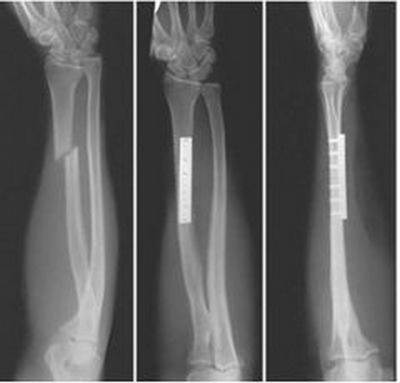

И вот таки рука стала сильно беспокоить и оказалось, что там сломана какая-то кость, которая по словам врачей (пока были у 2х) "единственная в теле человека, которая не срастается. Вообще..."

Предстоит операция, а мы совершенно не знаем что нас ждет! Что это за кость, которая не срастается? Что будут делать на операции? Вживлять пластину?